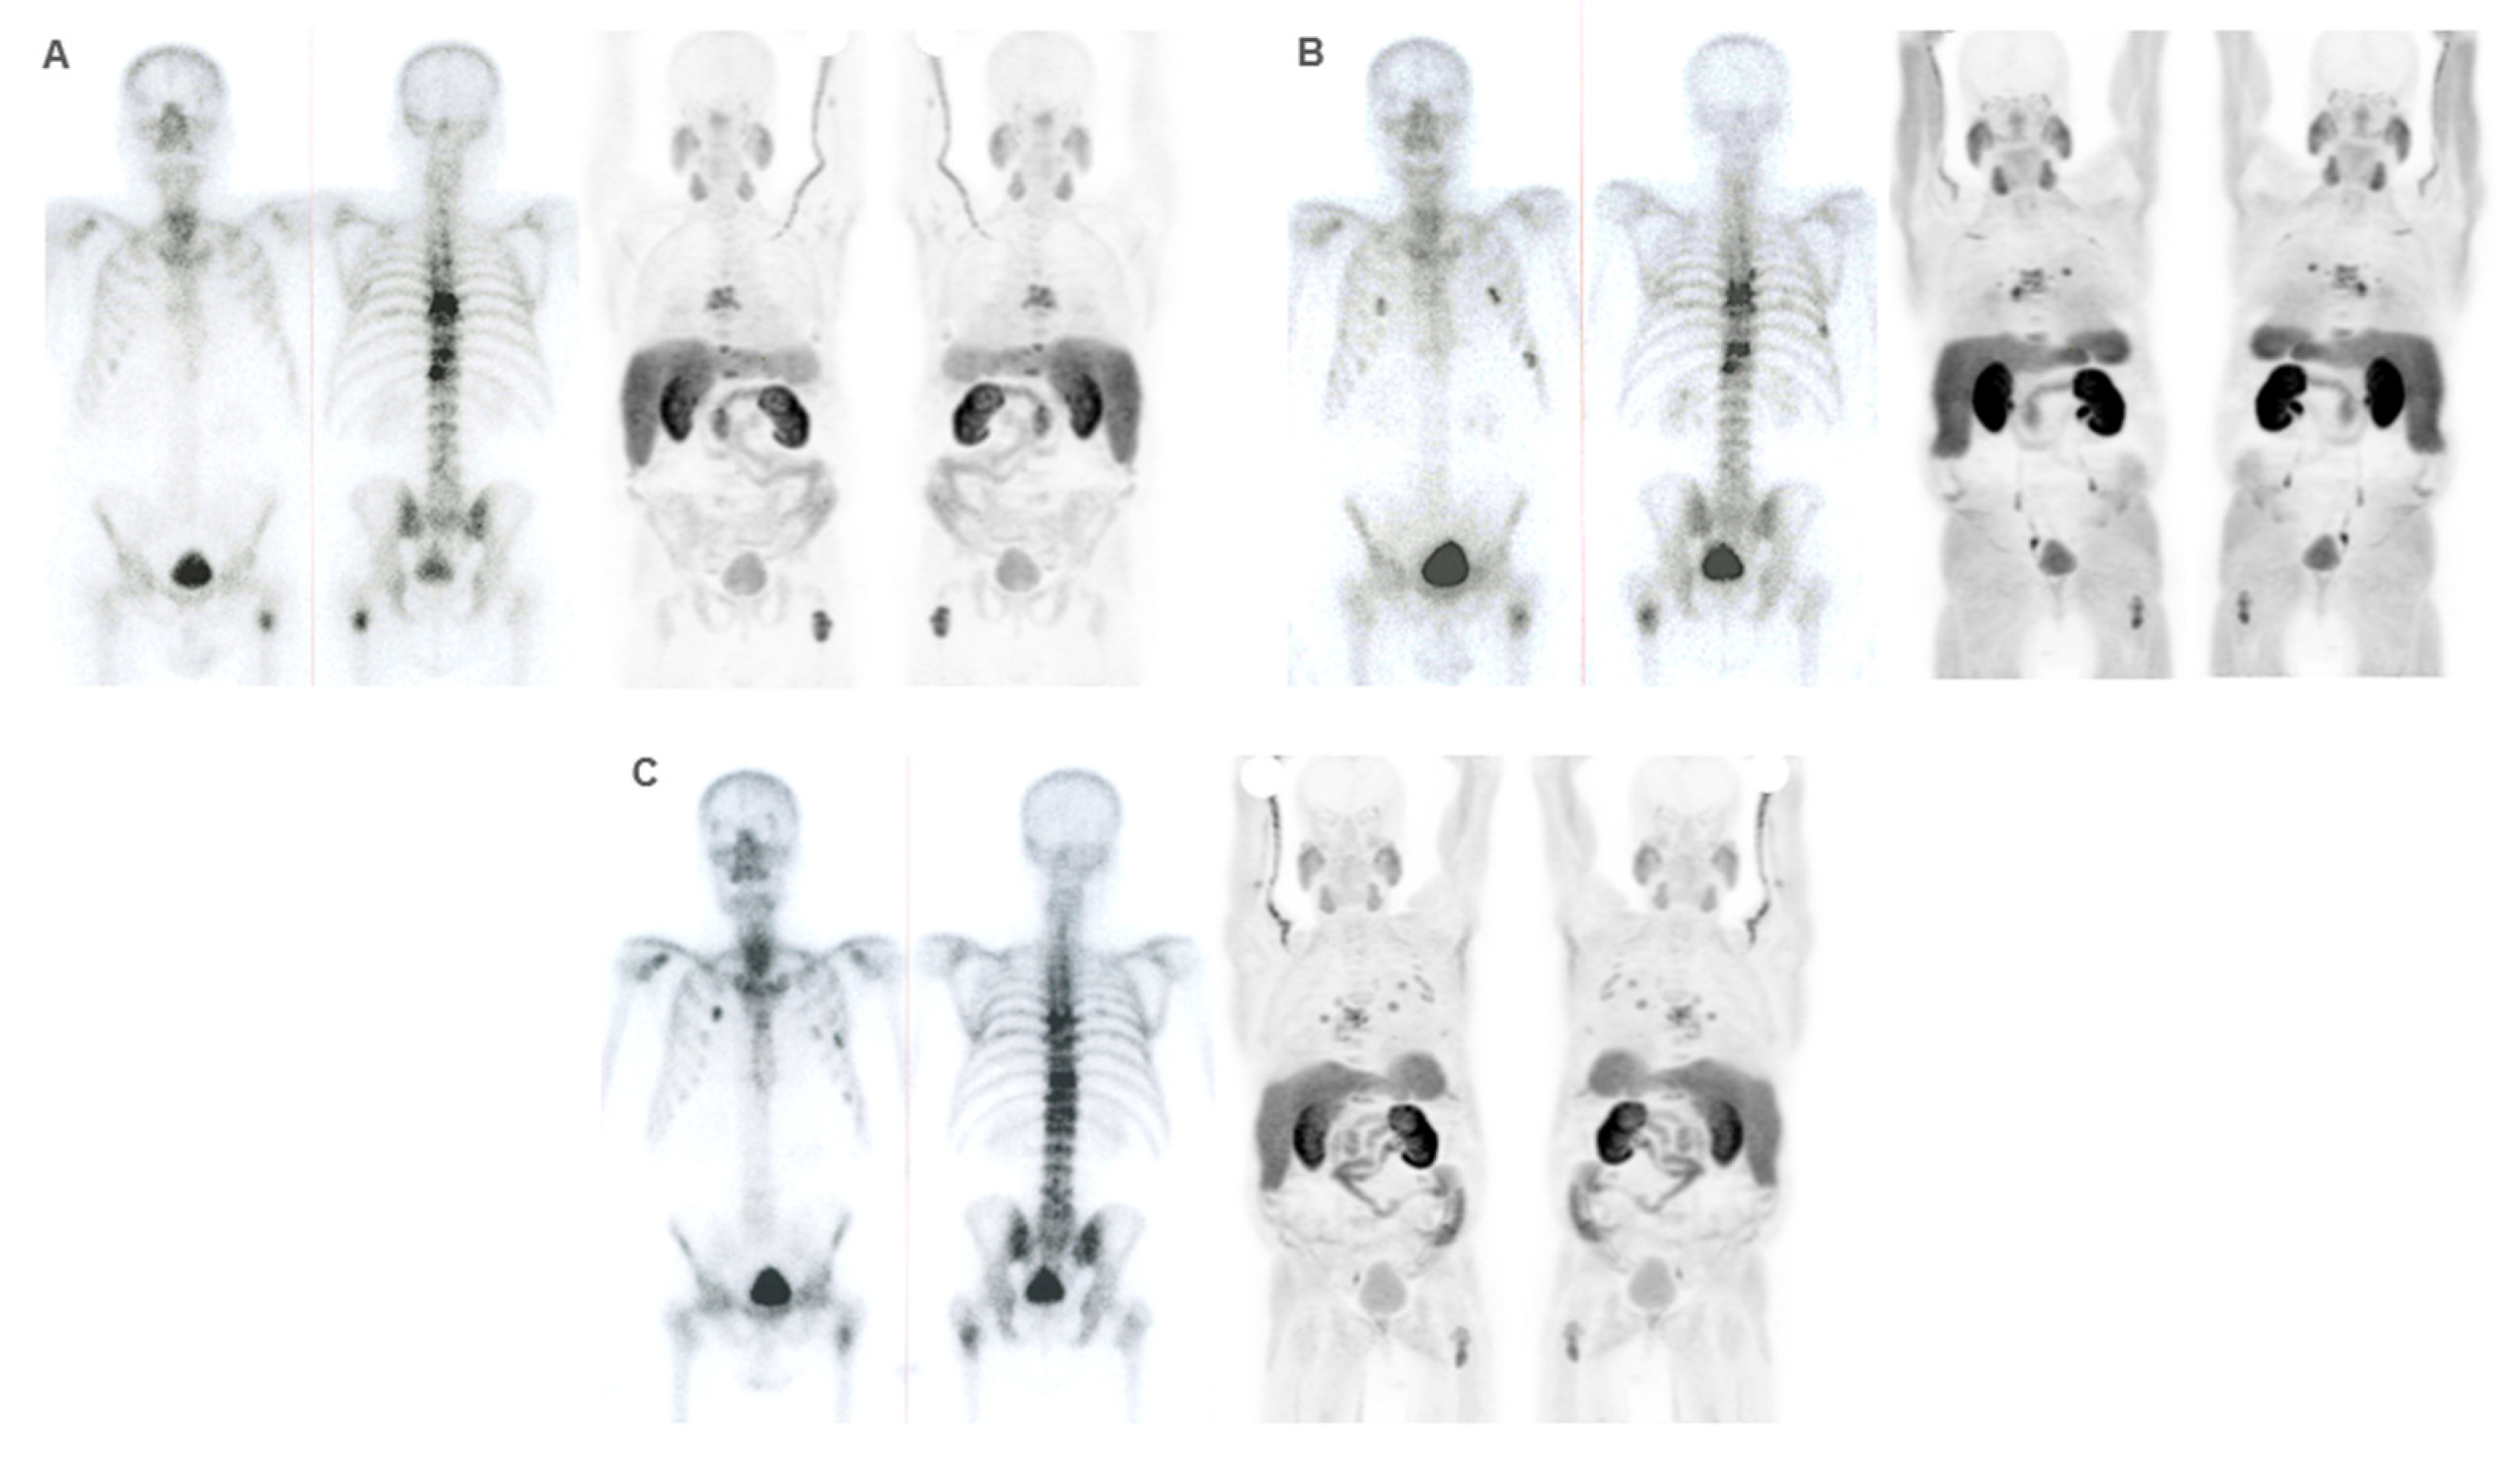

Diagnostic Imaging in Patient Selection

Response Assessment

Prognostic Factors